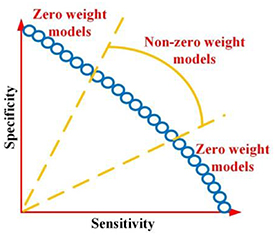

As predictive models are desired to have balanced sensitivity and specificity, the weight for the model with extremely imbalanced sensitivity and specificity is set as zero, whilst the weight for the remaining Pareto-optimal models are set as non-zero as shown in figure 5. As AUC is a good measurement for evaluating the model performance, it is considered for weight calculation as well. In summary, by considering the above two factors, the weight is calculated as:

Figure 5. Pareto-optimal model with two type weights.